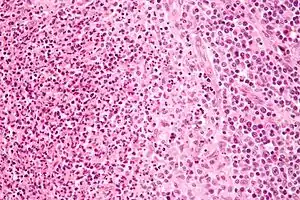

![]() Біоптат лімфатичного вузла з великою кількістю Bartonella henselae, з гранульомами (бліді клітини у правій частині зображення) й мікроабсцесами з нейтрофілів зліва від центру. (фарбування гематоксилін-еозином, велике збільшення) Біоптат лімфатичного вузла з великою кількістю Bartonella henselae, з гранульомами (бліді клітини у правій частині зображення) й мікроабсцесами з нейтрофілів зліва від центру. (фарбування гематоксилін-еозином, велике збільшення) | |

Через крайню рідкість летальних випадків патогенез вивчений недостатньо. Після потрапляння збудників у шкіру там розігрується обмежений некроз, який оточують численні макрофаги, часто багатоядерні гігантські клітини, лімфоцити та еозинофіли. Утворюються регіонарний до місця входження збудників лімфаденіт. Гістологічні зміни в уражених лімфовузлах характеризуються проліферацією гістіоцитів і В-лімфоцитів (стадія ретикулоклітинної гіперплазії), що приводить до утворення гранульом (гранульоматозна стадія) з подальшою нейтрофільною інфільтрацією і розвитком центрального або зірчастого некрозу (стадія мікроабсцедування). При дослідженні біоптатів типовою є комбінація в одній пробі гранульом та мікроабсцесів.